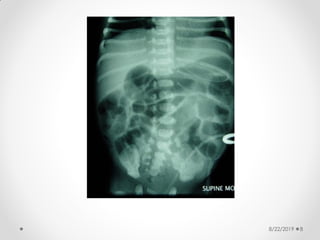

Pneumatosis intestinalis

8/22/2019 28

8/22/2019 29

Abdominal X-ray

findings:

• Dilated bowel loops

• Thickened bowel wall

• Fixed dilated loop

• Scarce or absent intestinal gas

• Pneumatosis intestinalis:

• radiologic sign pathognomonic of NEC

• appears as a characteristic train-track

lucency configuration within the bowel wall